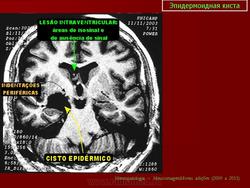

Эпидермоидная киста

Эпидермоидная киста.

Дифференциальная диагностика изображения